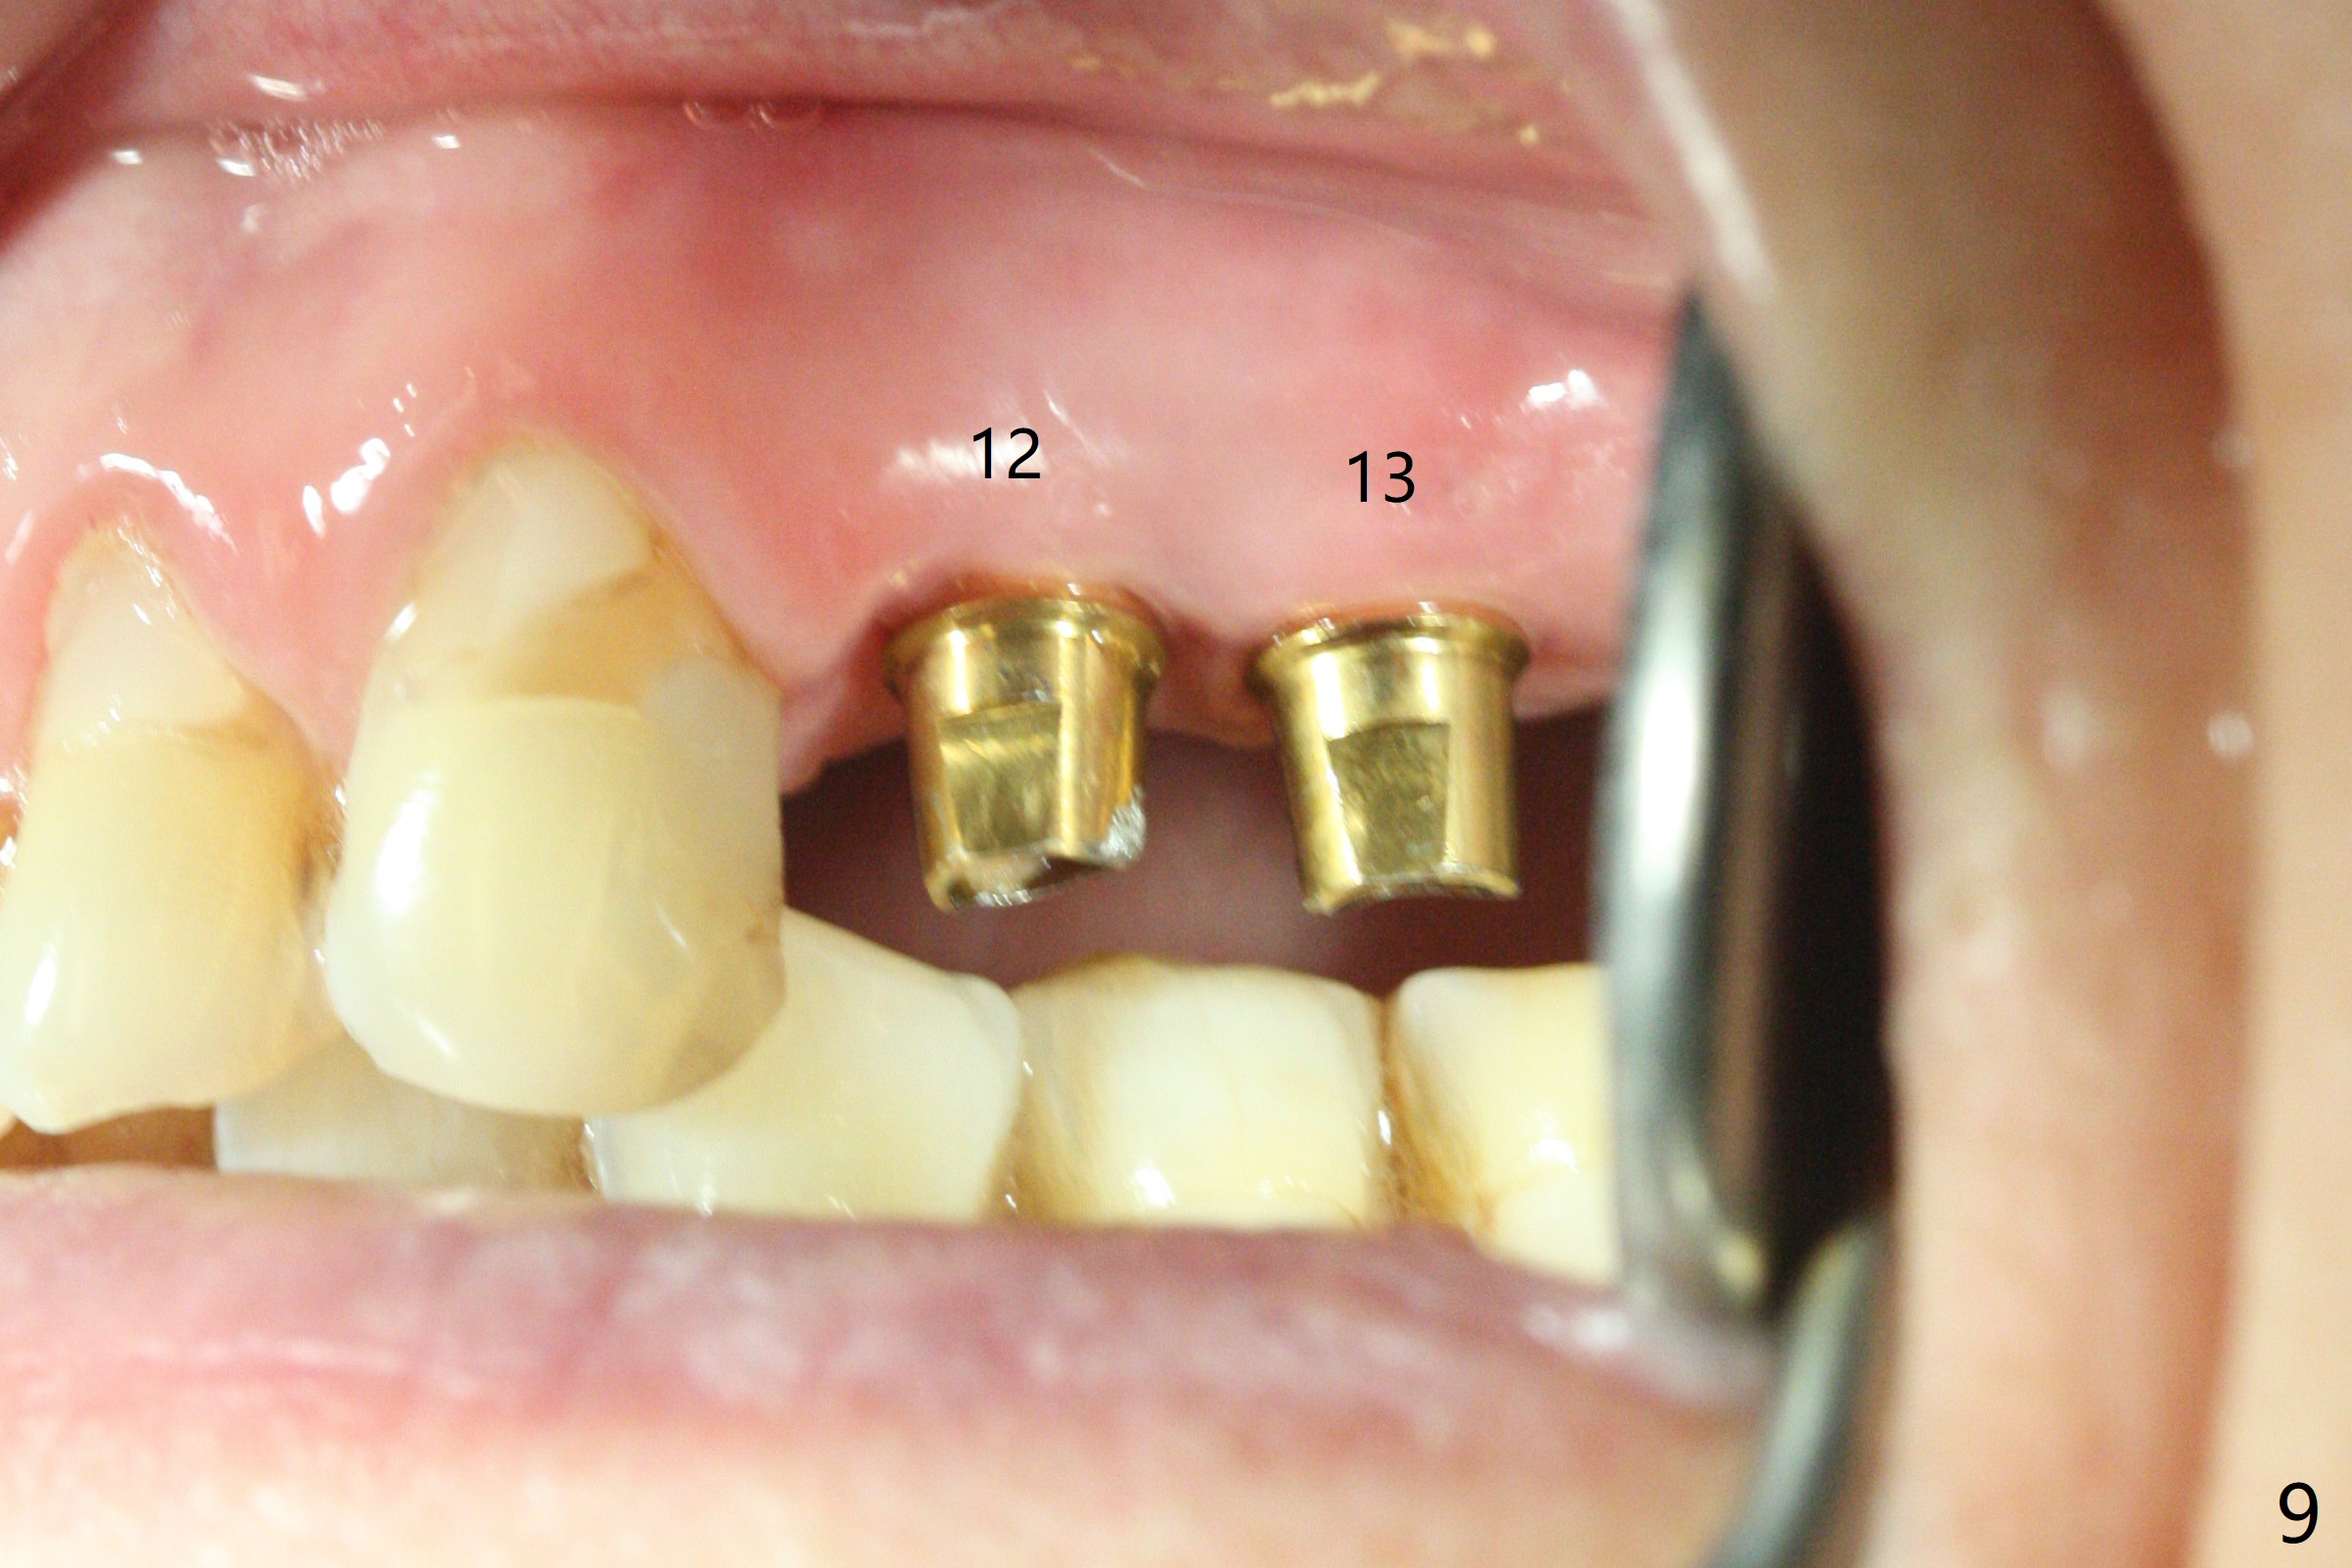

Osteotomy at #3 is performed last (Fig.1,2); as planned, a 4 mm cortical tap is used with guide for sinus lift. Unfortunately the sinus membrane is perforated. Implant placement is aborted. Instead Osteogen plug is inserted into the osteotomy, which is fixed in place by acrylic extending from the provisional at #4. Osteotomy for #3 implant will be attempted with control of the depth in 4 months. The patient has allergy to Amoxicillin (rash). When switching to Clindamycin, she develops diarrhea and loses 10 pounds. There is no abnormality at the site of #3 or 4 nearly 3 months postop (Fig.3). The next surgery will be most likely conducted without antibiotic 4 months postop. Try to draw blood for PRF. Take PA for #12 and 13 for possible impression. Remove the 3 temporary crowns, seat the guide across the arch and use no-stop fixture mounts at #4, and possibly 12 and 13. Follow the original drill sequence (check perforation after each drill, Fig.11) and use DIONavi sinus approach kit. Also load an appropriate stop for the round bur for sinus lift before hand. Mixture allograft with Metronidazole and PRF. In fact everything goes on as smoothly as planned. Osteotomy at #3 is underprep (3.5 mm in diameter drill instead of 4.0). The sinus floor appears to remain to be absent; 3.2 mm round bur is used for lift, alternating with water pumping. Following insertion of 3 pieces of PRF membranes and Vanilla Graft (Fig.4 *), a 4x10 mm dummy implant is placed. After additional bone graft (Fig.5 *), a final 4.5x7.3 mm implant is placed ~10 Ncm. The implant is placed deeper ~ 1 mm, followed by a 5.5x3 mm healing abutment (Fig.6). The implants at #12 and 13 seem to have osteointegrated (Fig.7). Impression is taken for #4, 12 and 13 with limited vertical space (Fig.8,9). An implant at #14 is being considered. There is faint bone graft around the apex of the implant 4 months postop (Fig.10). The implant sustains 25-30 Ncm torque when a 5.2x4(3) mm cemented abutment is placed. A permanent crown is cemented nearly 5 months postop (Fig.11). For the best cosmetic and masticating results, the occlusal surface should have certain degree of morphology, such as the buccal cusps (Fig.12 white curved lines). The abutment at #3 is placed and torqued to 30 Ncm before re-cementation of the repaired crown (increased occlusal surface contact). In fact the abutment at #4 is incompletely seated with a gap (Fig.13 <). The composite at #5 is dislodged while #3 crown is being repaired (*). The abutment at #4 is loose >1 year post cementation. The abutment remains incompletely seated (gap and longer apical space (double arrows)) when the abutment/crown complex rotates lingual mesiobuccal (Fig.14 curved arrow). Further proximal reduction and lingual rotation distobuccal leads to complete seating (Fig.15). It appears that incomplete seating at #13 is associated with hex mismatch (Fig.16, large apical space), which will be fixed next visit. One week later, the crown and abutment of #4 are seated together after crown repair (Fig.17). Since the abutment margin is subgingival, the crown is cemented, removed with abutment for residual cement removal and reseated with the abutment with torque at 30 Ncm. After this, the crown and abutment of #13 is reseated after mesiobuccal surface is trimmed (Fig.18), followed by pick up impression. A few days later, the crown/abutment are inserted together smoothly, the former cemented and the complex unscrewed for residual cement removal and last torqued at 30 Ncm without any X-ray confirmation.